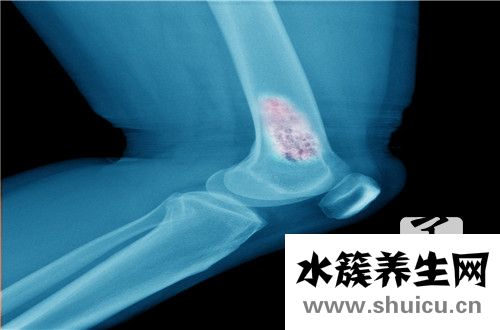

針對腓骨骨折的醫(yī)治,單純性選用內固定不動手術治療治療法會對病人造成一定的影響,如對病人部分的軟組織導致更大的損害,造成產生十分比較嚴重的手術后病發(fā)癥。運用外固定不動手術治療對腓骨骨折病人開展醫(yī)治,其骨折端平穩(wěn)實際效果不佳。除此之外,外固定不動手術治療會造成病人手術后出現(xiàn)多種多樣欠佳病癥,如骨節(jié)粘連、肌肉僵硬及功能問題等。近些年選用內外固定不動融合的治療法對腓骨骨折病人開展醫(yī)治,選用部分割開的方法,對蔓延到關節(jié)面的骨折注視下開展復位,部分內開展固定不動,另外選用骨外固定夾板開展外固定不動,具備固定不動跨距大、偶然性強等特性。根據選用內外固定不動融合療法治療腓骨骨折,既可以使病人骨折位置的可靠性明顯提高,另外可以顯著降低病人手術后病發(fā)癥的概率。從而可以合理地防止保守治療與單純性內固定不動的各種各樣缺點,減少了病人承擔的手術治療痛楚。